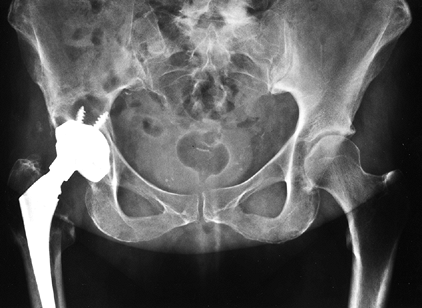

porous-coated femoral implants for patients with Dorr type A bone (Fig. 105.2), uncemented proximally coated metaphyseal filling implants for young patients with Dorr type B bone (Fig. 105-3), and cemented femoral

![]() |

Figure 105.2. AP radiograph of an uncemented total hip arthroplasty using an extensively porous-coated femoral component.